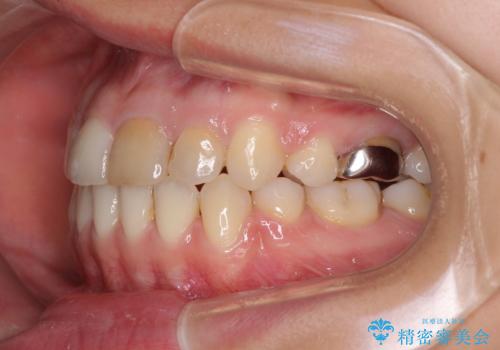

八重歯の抜歯矯正 費用を抑えた矯正装置

- 上の八重歯を気にして来院された患者様です。

受け口傾向にあるため、上顎前歯の叢生解消とともに下顎前歯を後方へ移動させることを目的とし、上下左右の第一小臼歯4歯を抜歯することとしました。